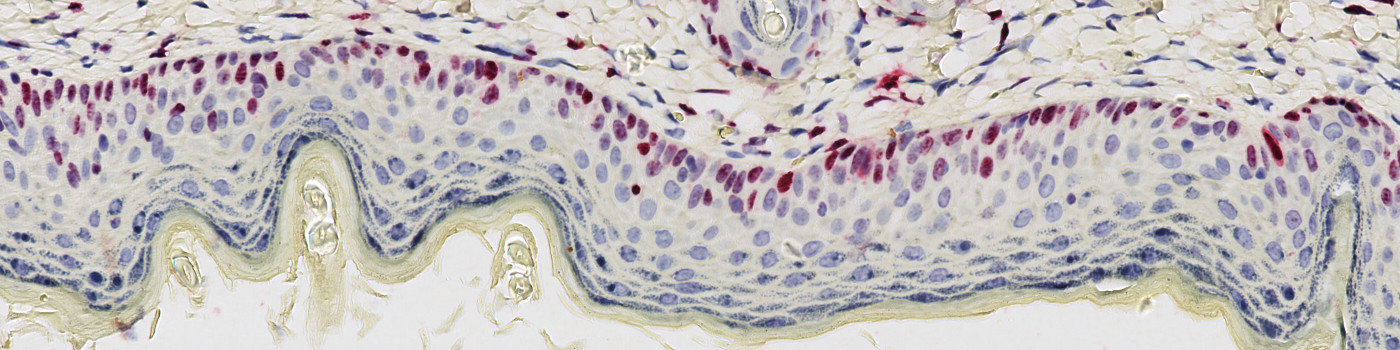

The Ki-67 protein is expressed in the nucleus and is a marker for cell proliferation. Increased number of Ki-67 positive cells in epidermis indicates increased epidermal hyperplasia, a characteristic which is associated with various inflammatory skin diseases as atopic dermatitis and psoriasis, see [1].

This protocol can be used to assess the number of Ki-67 positive cells in epidermis. The protocol provides the number and area of Ki-67 positive cells within the epidermis region, as well as for the entire tissue section. Manual assessment of the outlined epidermis region can be necessary.

The first image processing step is a rough outline of tissue. This is performed to limit the subsequent quantitative analysis and to facilitate numbering of tissue samples in cases with multiple samples per slide. The next processing step involves a segmentation of epidermis, followed by an exclusion of hair cells. The length of epidermis is calculated using the skeletonize feature. The rough outline and final region of interest (ROI) is seen in FIGURE 1 and 2, respectively. The final processing step includes a detection and quantification of positive nuclei in each ROI.